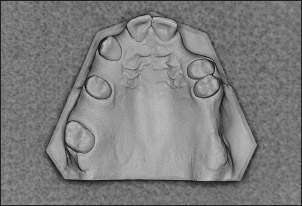

Fig 1-30 Maxillary Kennedy Class I, Modification 2 arch.

Fig 1-32 Maxillary Kennedy Class III, Modification 1 arch.

Fig 1-34 Maxillary Kennedy Class IV arch.

Fig 1-35 Maxillary Kennedy Class II, Modification 4 arch.